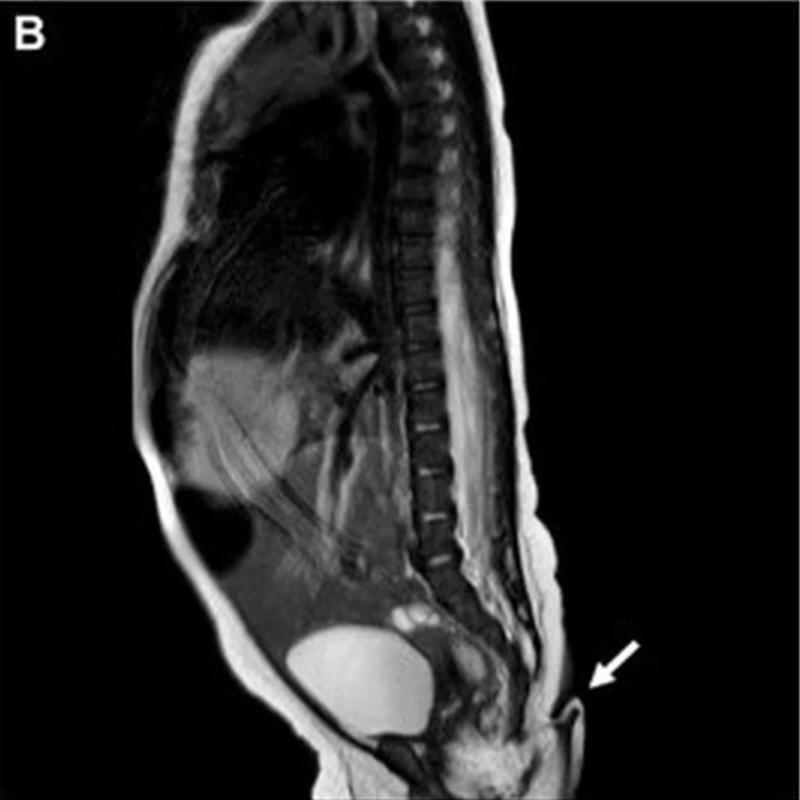

Luego de nacer, los médicos se percataron de que la menor tenía una cola en la hendidura interglútea, de 5,7 centímetros de largo y entre 3 y 5 mm de diámetro.

La cola era blanda, y estaba cubierta de piel y pelo fino. Parecía que no se movía por sí misma, por lo que los médicos la pincharon con una aguja. La bebé lloró, y así confirmaron que había conexión nerviosa.

Tras esto, examinaron a fondo a la cola, revelándose que se trataba de “tejido blando, incluyendo tejido fibroadiposo, estructuras vasculares y haces nerviosos, cubiertos por piel, sin alteraciones histopatológicas”.

Cabe señalar que según la división dada por Dao y Netsky en 1984, hay colas verdaderas y pseudocolas. Las verdaderas contienen tejido adiposo, conectivo y muscular, y no contienen vértebras o estructuras óseas.

En este caso, la cola no tenía estructura ósea, y tenía tejido adiposo y conectivo y muscular, por lo que se trataba de una verdadera cola humana.